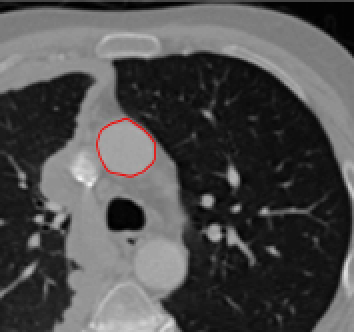

Four sets of test results are shown below. In Test 1 we compare models M1 – M6 to the proposed model M7 for two images which are hard to segment. The first is a CT scan from which we would like to segment the lower portion of the heart, the second is an MRI scan of a knee and we would like to segment the top of the Tibia. See Figure 9 for the test images and the marker sets used in the experiments. In Test 2 we will review the sensitivity of the proposed model to the main parameters. In Test 3 we will give several results achieved by the model using marker and anti-marker sets. In Test 4 we show the initialisation independence and marker independence of the Geodesic Model on real images.

Test 1 – Comparison of models M1 – M7.

In this test we give the segmentation results for models M1 – M7 for the two challenging test images shown in Figure 9. The marker and anti-marker sets used in the experiments are also shown in this figure. After extensive parameter tuning, the best final segmentation results for each of the models are shown in Figures 10 and 11. For M1 – M4 we obtain incorrect segmentations in both cases. In particular, the results of M2 and M4 are interesting as the former gives poor results for both images, and the latter gives a reasonable result for Test Image 1 and a poor result for Test Image 2. In the case of M2, the regularisation term includes the edge detector and the distance penalty term (see (4)). It is precisely this which permits the poor result in Figures 10(b) and 11(b) as the edge detector is zero along the contour and the fitting terms are satisfied there (both intensity and area constraints) – the distance term is not large enough to counteract the effect of these. In the case of M4, the distance term and edge detector are separated from the regulariser and are used to weight the Chan-Vese fitting terms (see (9)). The poor segmentation in Figure 11(b) is due to the Chan-Vese terms encouraging segmentation of bright objects (in this case), weighting ω𝜔\omega enforces these terms at all edges in the image and near \mathcal{M}. In experiments, we find that M4 performs well when the object to segment is of approximately the highest or lowest intensity in the image, however when this is not the case, results tend to be poor. We see that, in both cases, models M5 and M6 give much improved results to M2 and M4 (obtained by incorporating the geodesic distance penalty into each). The proposed Geodesic Model M7 gives an accurate segmentation in both cases. It remains to compare M5, M6 and M7. We see that M5 is a non-convex model (and cannot be made convex [39]), therefore results are initialisation dependent. It also requires one more parameter than M6 and M7, and an accurate set \mathcal{M} to give a reasonable area constraint in (4). These limitations lead us to conclude M6 and M7 are better choices than M5. In the case of M6, it has the same number of parameters as M7 and gives good results. M6 can be viewed as the model M7 with weighted intensity fitting terms (compare (18) and (30)). Experimentally, we find that the same quality of segmentation result can be achieved with both models generally, however M6 is more parameter sensitive than M7. This can be seen in the parameter map in Figure 12 with M7 giving an accurate result for a wider range of parameters than M6. To show the improvement of M7 over previous models, we also give an image in Figure 13 which can be accurately segmented with M7 but the correct result is never achieved with M6 (or M3). Therefore we find that M7 outperforms all other models tested M1 – M6.